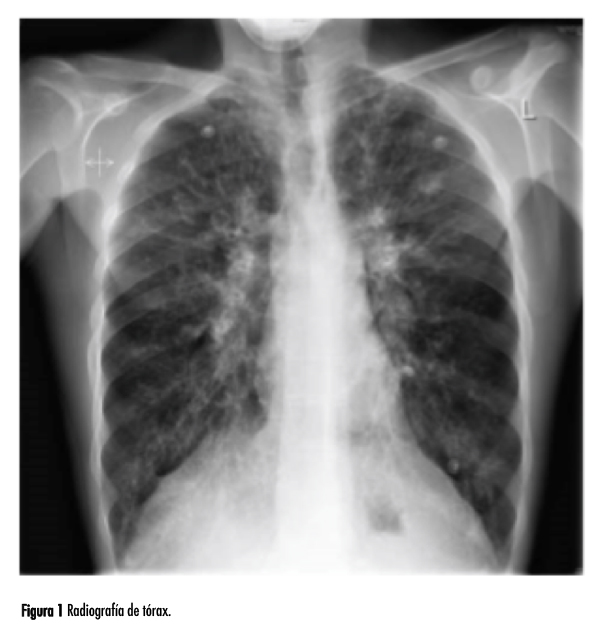

La radiografía de tórax se muestra en la figura 1.

La radiografía de tórax muestra sombras anormales en ambos pulmones, más marcadas en los dos lóbulos superiores, con algunas sombras en anillo y sombras tubulares que representan paredes bronquiales engrosadas. Estos datos serían compatibles con un diagnóstico de bronquiectasia. Las arterias pulmonares son prominentes, lo que sugiere un grado de hipertensión pulmonar. La distribución es típica de la que se encuentra en la fibrosis quística, donde los cambios son más evidentes en los lóbulos superiores. La mayoría de las otras formas de bronquiectasias tienen más probabilidades de ocurrir en los lóbulos inferiores, donde el drenaje por gravedad es menos eficaz. La tomografía computarizada (TC) de alta resolución de los pulmones es la mejor manera de diagnosticar la bronquiectasia y definir su extensión y distribución. En pacientes más jóvenes y casos leves de fibrosis quística, los microorganismos predominantes en el esputo son Haemophilus influenzae y Staphylococcus aureus. Más tarde, a medida que se produce más daño pulmonar, Pseudomonas aeruginosa es un patógeno común. Una vez presente en los pulmones en la fibrosis quística, es difícil o imposible eliminarla por completo.